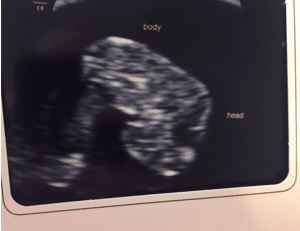

Hello Blurry Bob #2! Watch my Instagram @runningshoesandreesieroo for new photos! We have our big ultrasound on Friday!